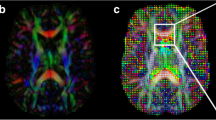

MR images of 70 patients treated with Gamma Knife SRS for WHO grade I meningiomas were retrospectively reviewed. MR acquisition included pre- and post-treatment DWI and DTI sequences, and subtractions were calculated to assess for radiation-induced changes in the parameter values.

After a mean follow-up period (FUP) of 52.7 months, 69 of 70 meningiomas were controlled, with a mean volume reduction of 34.9%. Whereas fractional anisotropy (FA) values of the initial exam showed the highest correlation to tumor volume change at the last FU (CC = − 0.607), followed by the differences between first and second FU values of FA (CC = − 0.404) and the first longitudinal diffusivity (LD) value (CC = − 0.375), the correlation coefficients of all ADC values were comparably low. Nevertheless, all these correlations, except for ADC measured at the first follow-up, reached significance.